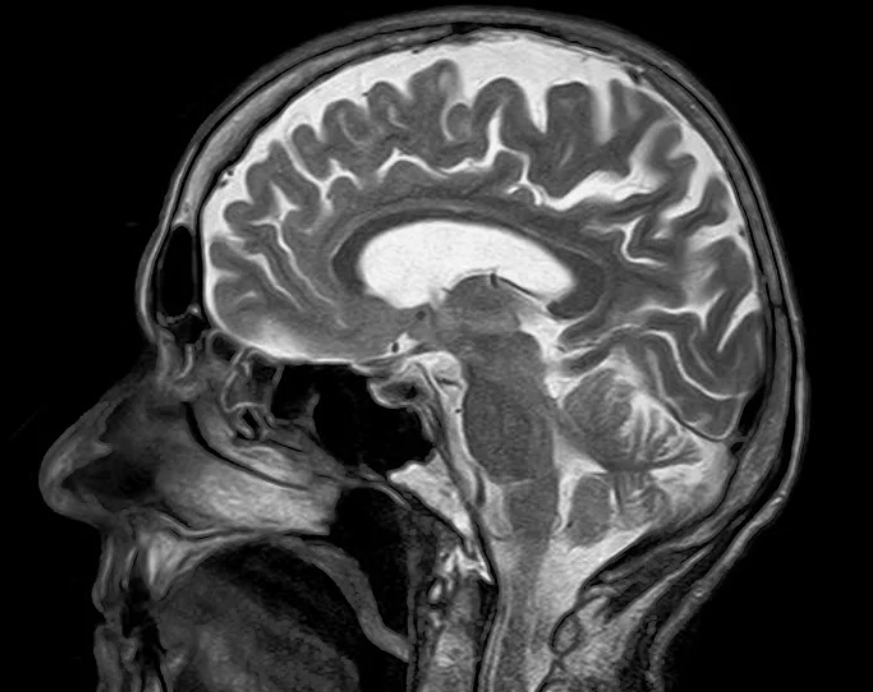

의사는 광범위한 의학적 상황을 진단할 수 있도록 CT 스캔이나 MRI 스캔을 주문합니다.두 가지 스캔은 용도가 비슷하지만 CT 스캔은 X선을, MRI 스캔은 강한 자기장과 전파를 사용합니다.CT 스캔이 더 보편적이고 저렴하지만 MRI 스캔은 더 자세한 이미지를 생성할 수 있습니다.

이 스캐너는 전파와 자석을 사용하여 이미지 MRI 스캐너를 만듭니다. MRI 스캐너는 일정한 자기장을 발생시키는 기계입니다. 이것은 전파를 이용하여 체내의 물 분자와 지방 세포를 사출합니다. 스캐너도 이미지를 컴퓨터로 전송합니다.CT촬영은 MRI보다 더 흔하고 비용도 저렴합니다.

하지만 CT 스캔 영상보다 MRI 스캔이 더 좋습니다.CT와 MRI 촬영은 비용이 저렴하고 디테일이 좋으니까요.의사는 보다 정확하고 상세한 신체영상을 제작해야 할 때 MRI 촬영을 주문할 수 있습니다.

MRI검사에서 더 쉽게 볼 수 있는 문제점으로는 연조직 손상, 찢어진 인대, 디스크 등의 의사가 신체부위의 일반화 영상이나 장기 또는 두부 골절 영상을 만들기 위해 CT검사를 이용할 수 있습니다.CT 스캔과 MRI 스캔은 신체 내부 부위를 촬영하는 두 가지 방법입니다.용도는 비슷하지만 촬영 방법이 다릅니다.

CT 스캔은 엑스레이를 사용하지만 MRI 스캔은 강한 자석과 전파를 사용합니다.CT 스캔은 일반적으로 큰 부위에 좋은 반면 MRI 스캔은 전체적인 이미지를 비교적 잘 만들어냅니다.둘 다 위험은 있지만 상대적으로 안전한 수술입니다.의사는 어떤 스캔이 사람에게 적합한지 요소별로 추천합니다.